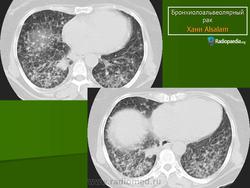

Бронхиолоальвеолярный рак

Бронхиолоальвеолярный  рак, рассматривается, как вариант переферической аденокарциномы. Патогномоничным  симптомом считают выделение большого количества (до 2-х литров в сутки) слизистой пенистой мокроты. Симптом встречается редко.